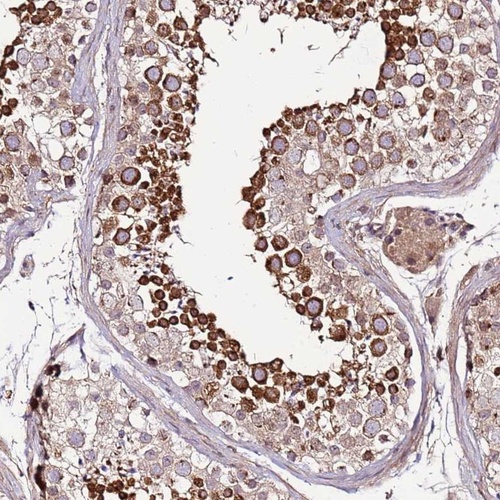

Immunohistochemical staining of human testis shows strong cytoplasmic positivity in cells in seminiferus ducts.